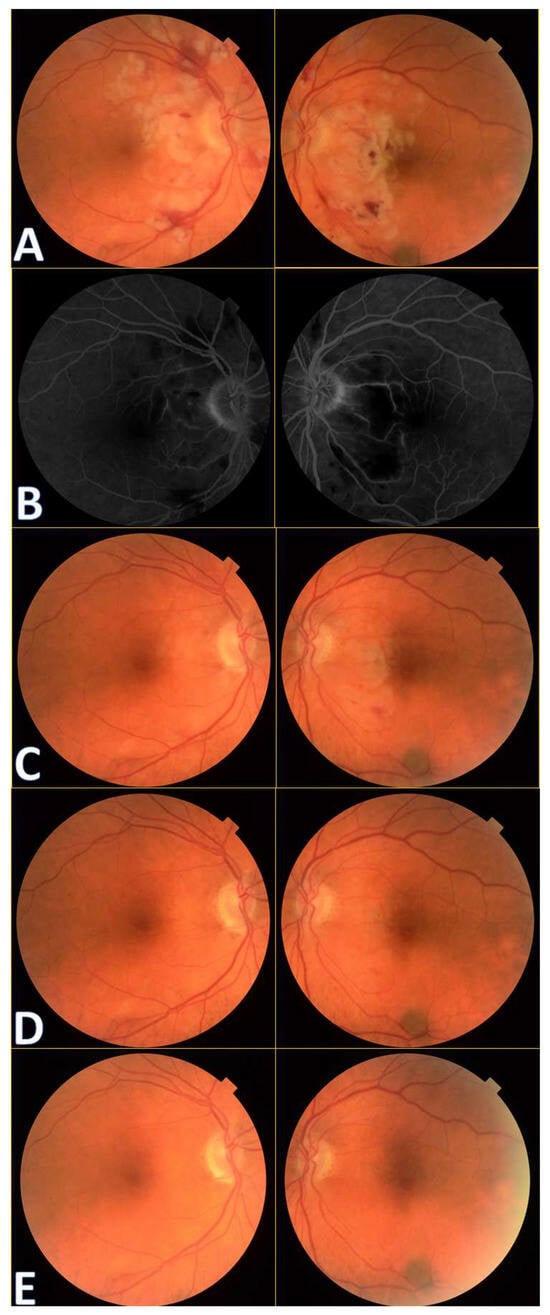

Figure 1.

Colour fundus photography of the patients with Purtscher retinopathy shows cotton wool spots in the papillo-macular bundle region, retinal hemorrhages, and Purtscher flecken at initial presentation (A). A benign choroidal nevus can also be noticed bordering the inferotemporal vascular arcade in the left eye.

A 72-year-old female presented to the Ophthalmology Department 7 days after a traffic accident. The ophthalmologic examination revealed the best corrected visual acuity (BCVA) of counting fingers (CF) in both eyes. Intraocular pressure in both eyes remained within normal range. The anterior segment evaluation did not reveal any abnormalities. The patient was admitted to the ward for prompt intravenous infusion of methylprednisolone, pentoxifylline, and fluid therapy. Additionally, she received dexamethasone and nepafenac eyedrops, antihypertensive drugs, and oral acetazolamide to improve the blood supply to the posterior pole of the eyeball. She was also administered with low-molecular-weight heparin and vitamins (B1, B6, B12) subcutaneously daily. Fluorescein angiography (Figure 1B) performed on the next day after the patient’s admission to the Ophthalmology Department demonstrated bilateral hypoperfusion of the posterior pole with subtle vessel leakage and hyperfluorescence of the optic disc margin in the temporal quadrant. On day 4 of hospitalization, a significant improvement in retinal morphology was observed, but visual acuity was still at the level of counting fingers at a slightly greater distance. After being discharged, she was switched to oral steroids, which decreased gradually in time, and then the supplementation of citicoline 500 mg daily was added. Follow-up at 1 month (Figure 1C) illustrated major resolution of pathological changes in time. Already after 2 months, the eye fundi looked almost normal (Figure 1D). At 6 months, the view was slightly opaque because of the accelerated development of cataract (Figure 1E). The final BCVA of the patient was 20/160 in the right eye and 20/63 in the left eye. The patient was also monitored using perimetry and optical coherence tomography (OCT) (Figure 2 and Figure 3). OCT-Angiography did not reveal any relevant abnormalities in the superficial and deep plexuses, nor in the choriocapillaris layer throughout the observation period. Multifocal electroretinography and visually evoked potentials were additionally performed (Figure 4).